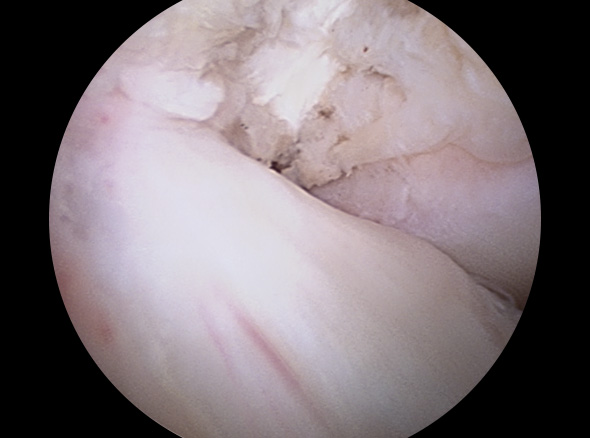

이식할 인대 삽입

이식한 인대 고정